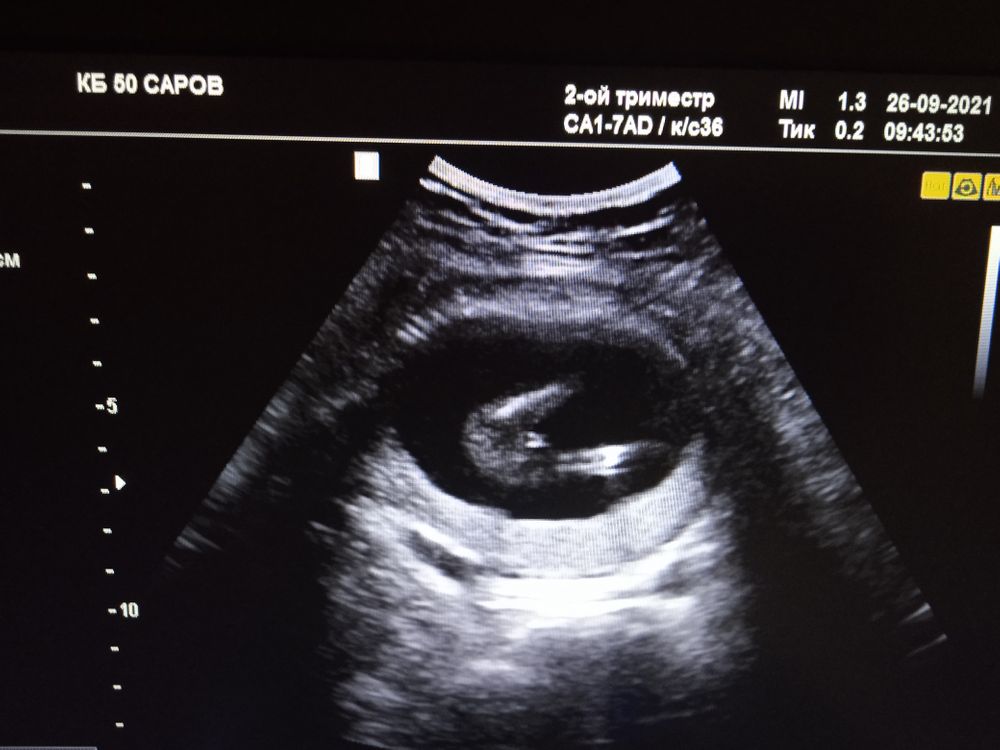

Узи 17 недель

Изображение Изображение Изображение Мальчик чуть больше 15 недель, на фото больше на девочку похоже🤗

Думаю, девочка.

Вроде мальчик

Я девочку вижу